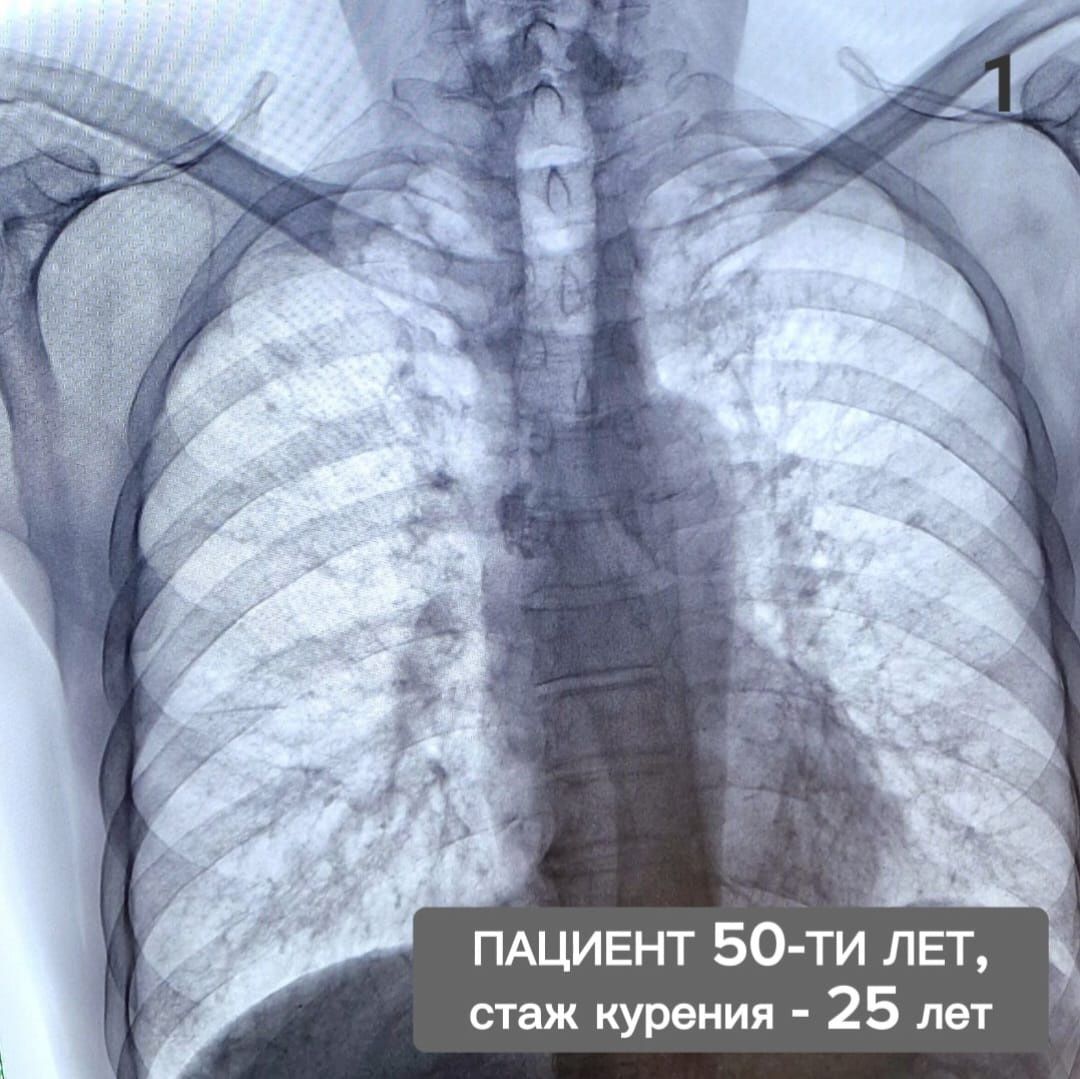

На одном снимке легкие курильщика с 25-летним стажем, на втором – мужчины, который курил 15 лет, а потом бросил. Рентгенографию прошли мужчины-ровесники. Им по 50 лет.

«Первый не может, не задыхаясь, подняться на 3 этаж, второй – уже 5 лет ходит в пешие походы по самым живописным уголкам страны. Главное отличие в том, что один пациент прислушался к советам врачей: отказался от вредной привычки и теперь дышит полной грудью, другой - страдает хроническим бронхитом, пневмосклерозом, одышкой, имеет нарушение сердечного ритма. При этом утверждает, что ему легче, когда он переходит на электронные сигареты», - рассказал Рамзиль Гильметдинов.